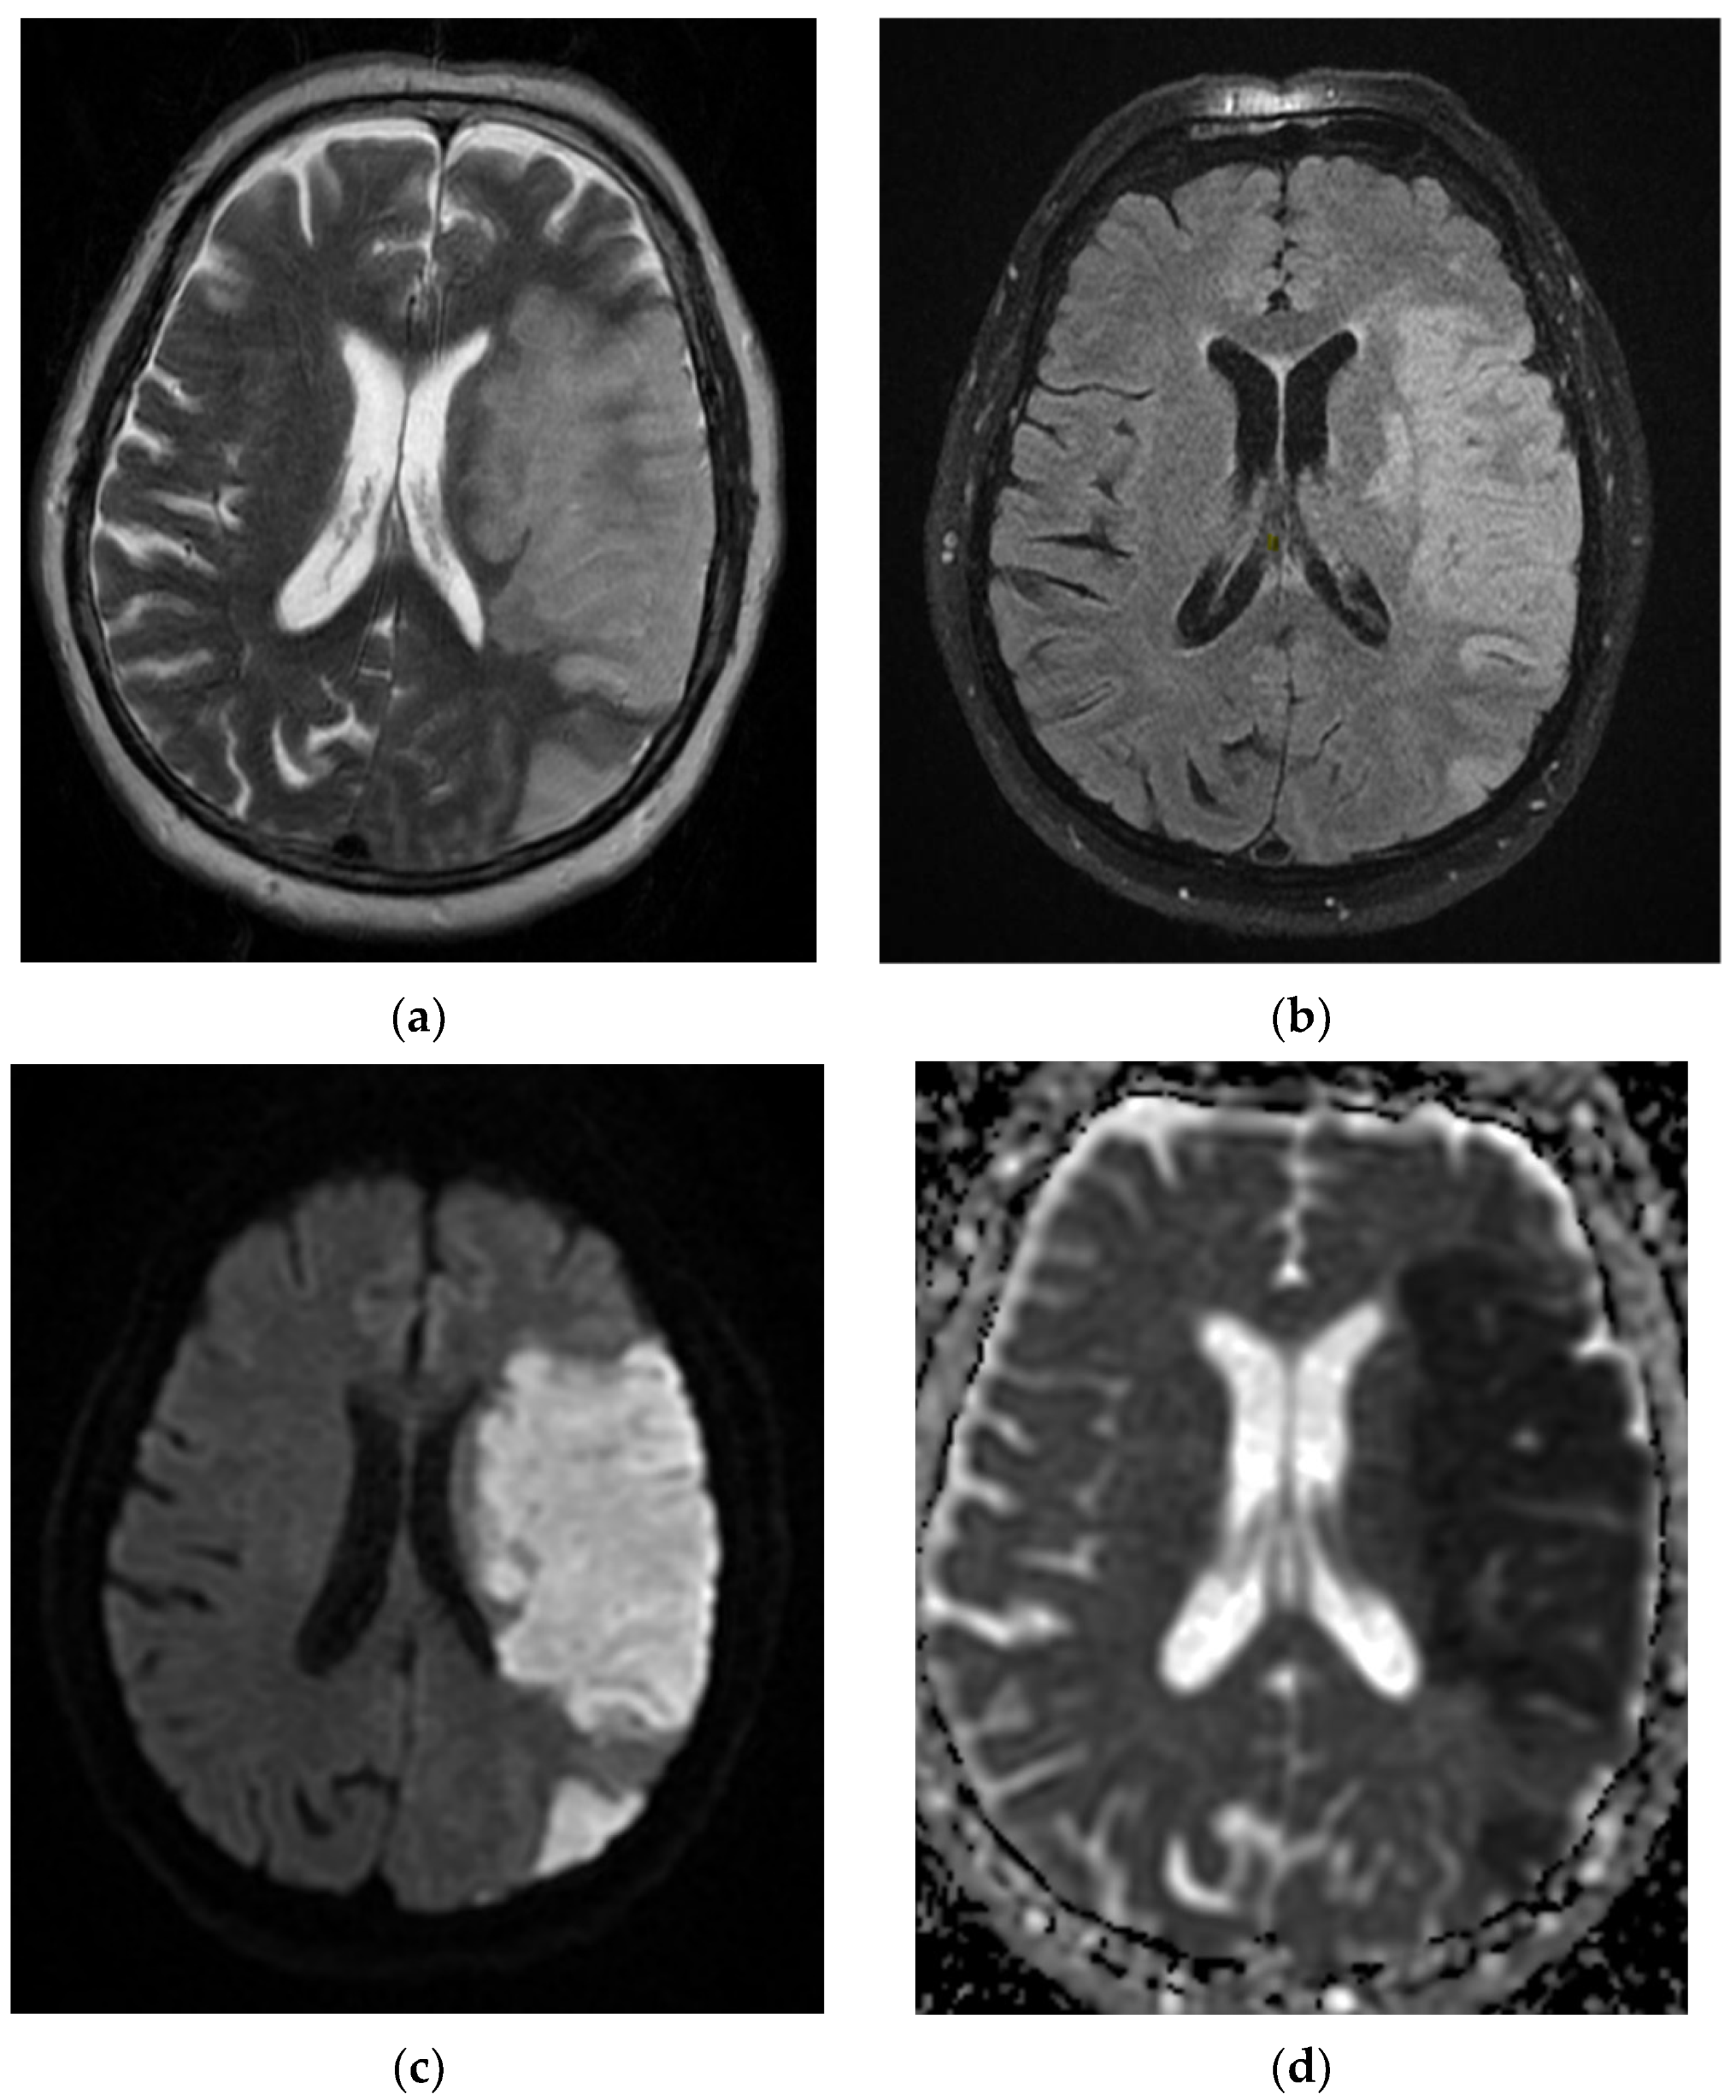

Figure 14. After 11 days from the first pulmonary CT, the cranio-cerebral MRI in the Case 10 patient showed foreshadowing of intense T2 signal (a), with deposits of predominantly peripheral methemoglobin (b), deficient restriction of diffusion (c,d) and gyriform gadolinium I (e), developed in the cortical–subcortical–occipital left median side with extension in the thalamic nucleus on the same part. In conclusion, infarction hemorrhagically transformed into superficial and profound territories of the left posterior cerebral artery.

A recently infected 72-year-old elderly patient with a severe form of COVID-19 was transferred from the Cardiology department with acute fibro flutter, and a recent brain CT (admission from Infectious Diseases Hospital) showed left ischemic PCA stroke appearance, with a brain MRI describing a left ischemic ACP stroke that transformed into hemorrhagic stroke, present during acute COVID-19 infection and post-hospitalization at home with bilateral lower limb plegic motor deficit.

Neurological objective assessment on admission showed the patient to be conscious, partially cooperative, and partially temporospatially oriented, with a right-upper-limb motor deficit, flaccid paraplegia, abolished osteotendinous reflexes in the lower limbs, and no tactile surface sensitivity disorders. During hospitalization, she underwent native and contrast-enhanced chest CT scanning, which showed alveolo-interstitial changes suggestive of post-COVID-19 status, lumbar puncture (CSF macro- and microscopically normal appearance), and a thoracolumbar spine MRI showing a left minor split disc L5-S1 with a subligamentary nonmigrated pulposus nuclear fragment. Biological tests revealed liver cytolysis, hypokalemia, and corrected hyperglycemia. During hospitalization, she was treated with statin, antiplatelet, and hydration infusion solutions, with unfavorable evolution. The patient suffered cardio-respiratory arrest (Figure 10, Figure 11, Figure 12, Figure 13 and Figure 14).